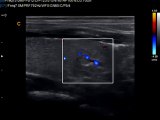

Chison Q9 Median nerve

How to find Median Nerve - Chison Q9 Median Nerve Short Video

Median Nerve with Chison Q9 Color Ultrasound

How to find median nerve with Chison Q9 Color Doppler Ultrasound